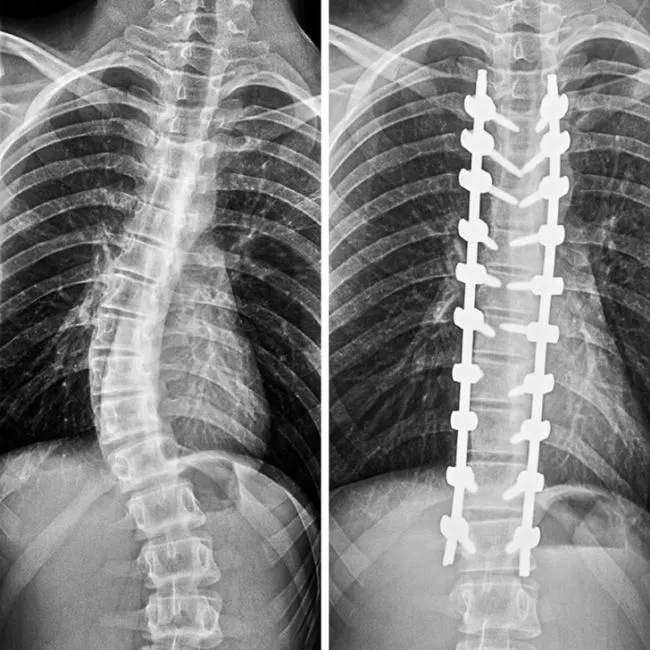

“ นี่คือลักษณะที่กระดูกสันหลังของฉันดูเหมือนจากผ่าแก้กระดูกคด”

© erich0779 / reddit